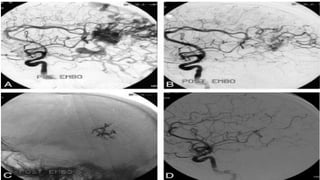

Embolization

•Skilled catheterization permits selective embolization of

feeding vessels with isobutyl-cyanoacrylate, although this

technique is not without risk. Embolization may cure up to 40%

of AVMs when small particularly if supplied by a single feeding

vessel, but filling may persist from collaterals. When used

preoperatively, it may significantly aid operative removal.

Endovascular Treatment of Cerebellar Arteriovenous Malformations: A Single-

Centre Experience of 75 Consecutive Patients

Yong Sun et al (2020) conducted a study to determine the safety and

effectiveness of endovascular treatment for cerebellar arteriovenous

malformations (AVMs). 75 patients with cerebellar AVMs who underwent

endovascular treatment were included. 61 (81.3%) presented with initial

hemorrhage, and 44 (58.7%) presented with 63 cerebral aneurysms. Immediate

digital subtraction angiography (DSA) after the procedure showed complete

occlusion of the cerebral aneurysms in all the patients, and total occlusion of the

AVM nidus in 32/75 (42.7%) patients, 99–90% occlusion in 31/75 (41.3%)

patients, and <90% occlusion in 12/75 (16.0%) patients. The study concluded that

endovascular treatment of cerebellar AVMs is safe and feasible. The high rate of

associated cerebral aneurysms could explain the tendency of initial hemorrhage

in cerebellar AVMs; targeted embolization of coexisting cerebral aneurysms

should be the first priority. Increasing patient age, eloquent AVM location, and

the size of AVM are independent predictors of poor outcome after endovascular

treatment of cerebellar AVMs.